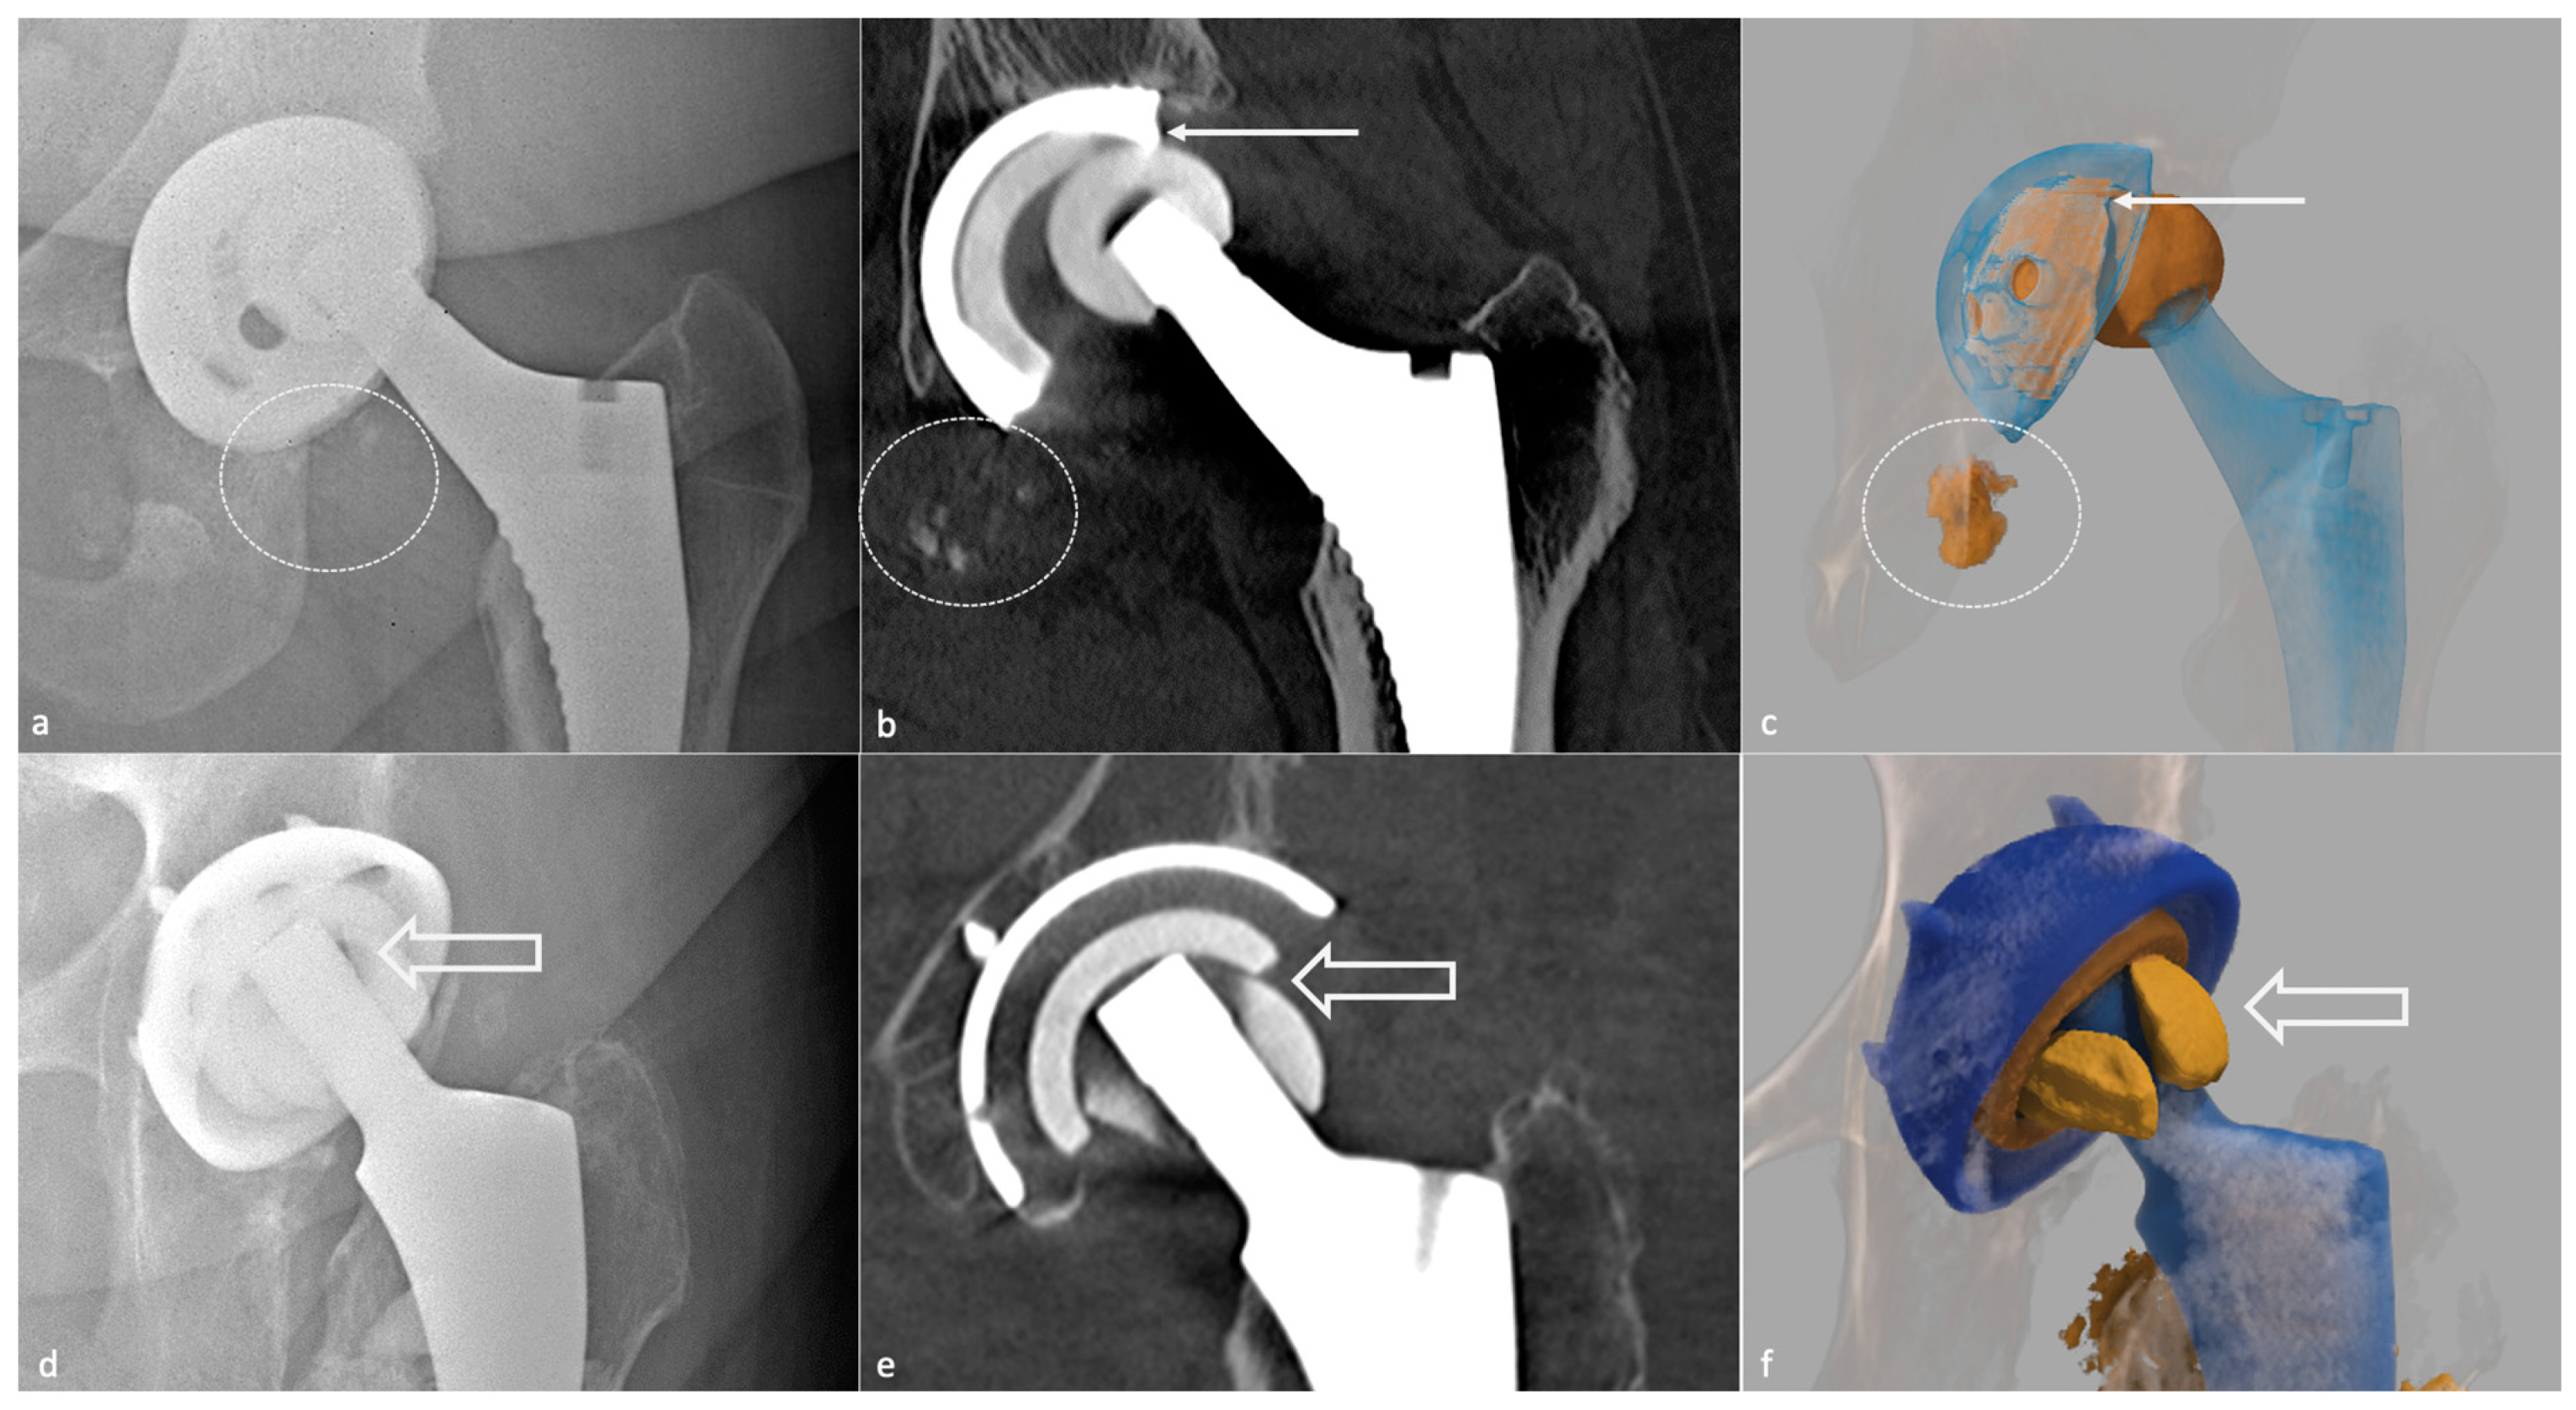

- Sutphen, S.A.; Lipman, J.D.; Jerabek, S.A.; Mayman, D.J.; Esposito, C.I. Treatment of Recurrent Dislocation after Total Hip Arthroplasty Using Advanced Imaging and Three-Dimensional Modeling Techniques: A Case Series. HSS J. 2020, 16, 245–255. [Google Scholar] [CrossRef]

- De Martino, I.; D’Apolito, R.; Waddell, B.S.; McLawhorn, A.S.; Sculco, P.K.; Sculco, T.P. Early Intraprosthetic Dislocation in Dual-Mobility Implants: A Systematic Review. Arthroplast. Today 2017, 3, 197–202. [Google Scholar] [CrossRef] [PubMed]